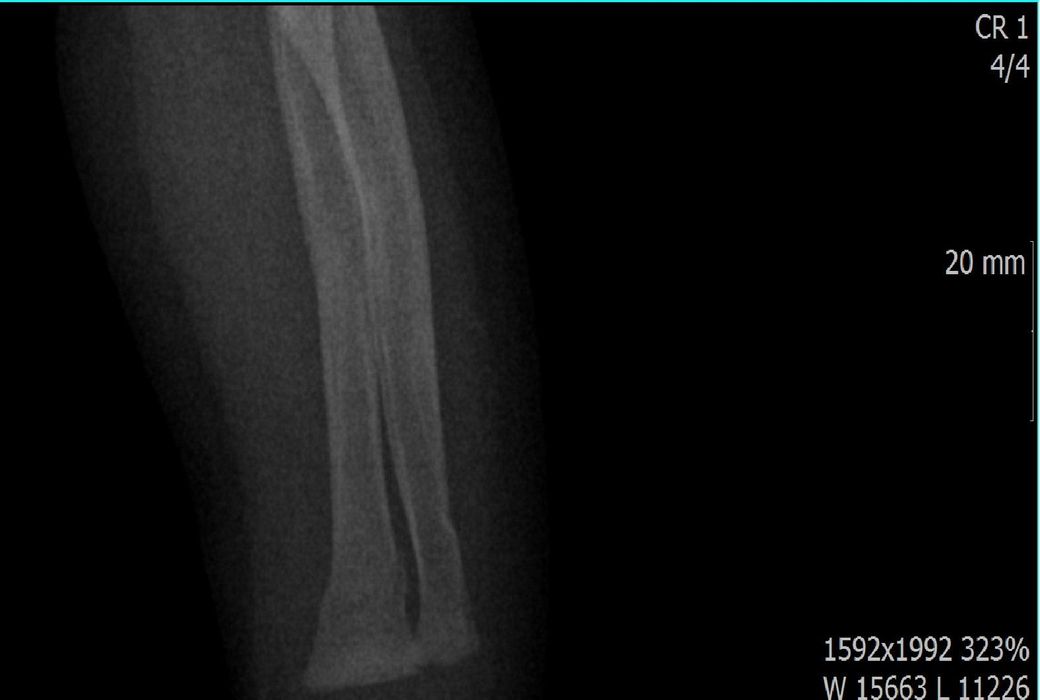

• 2번 째 사진

단지 2번째 사진을 보면 척골이 완전히 부러져서 어긋나 있는 것이 보이지요? 통증이 심했을 것이며 (환자분이 어린 것 같은데 증상 호소가 더 심했겠지요) 팔이 많이 부었을 것입니다. 증상을 기준으로 생각하시면 더 정확하실 것 같습니다.